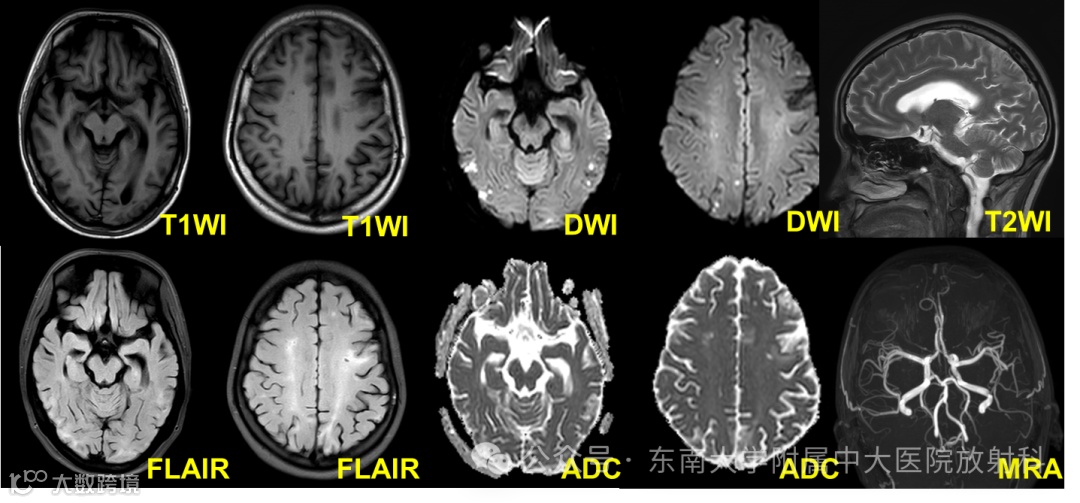

影像学检查: 2024-08-26 颅脑MRI平扫

2024-09-29 颅脑MRI+MRA

影像学表现